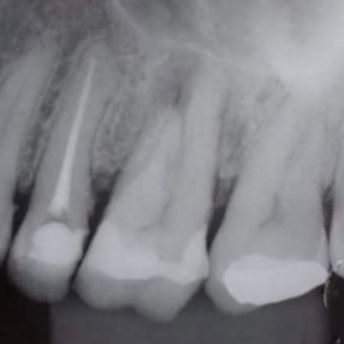

Câmera Intraoral;

Rx portatil;

Sensor rx;